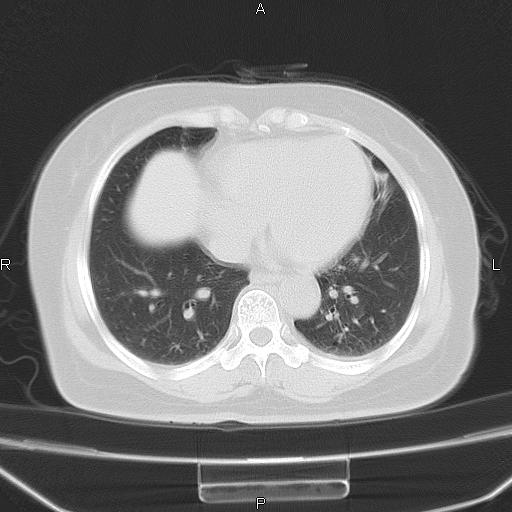

胸腺瘤

女、63Y 双眼睑下垂,早轻晚重。 胸腺瘤???

结果胸腺瘤